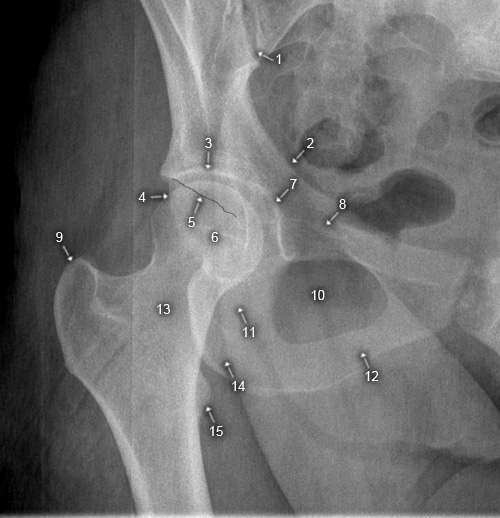

Foramen obturatum

1. Articulatio sacroiliaca

2. Linea terminalis

3. Pfannendach

4. hinterer Pfannenrand

5. vorderer Pfannenrand

6. Caput femoris

7. vorderer Pfannengrund

8. Corpus ossis pubis

9. Trochanter major

10. Foramen obturatum

11. Corpus ossis ischii

12. R. inferior ossis pubis

13. Collum femoris

14. Tuber ischiadicum

15. Trochanter minor